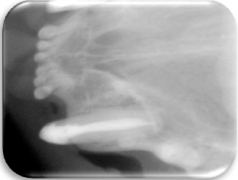

- Radiográfico (analógico y digital)

El diagnóstico clínico oral es de suma importancia ya que el plan de tratamiento y el pronóstico dependen de un certero y profundo análisis de los signos de la cavidad oral. Nuestra principal preocupación es atender los problemas que se encuentran en cavidad oral pero además siempre realizamos un detallado análisis de la función general del paciente. En nuestro centro revisamos de manera general a la mascota detectando cualquier problema sistémico. Contamos con un laboratorio de análisis clínicos en donde se realizan biometría hemática, química sanguínea, examen general de orina y pruebas para detección de enfermedades virales y de otros microorganismos. Contamos también con un laboratorio de histopatología en donde se revisa el material biológico para la detección y el diagnóstico de cambios morfológicos y lesiones en los tejidos. En lo que respecta al diagnóstico de la boca, contamos con un expediente donde se vacía toda la información dental y bucal de tal manera que mantenemos el control del tratamiento odontológico desde el inicio hasta el final y en donde el propietario o el médico que nos recomienda puede revisar en detalle toda la información recabada. Contamos con todo el instrumental y el equipo necesario para el diagnóstico de el aparato estomatognático (cavidad oral con dientes, tejidos de sostén y tejidos blandos, además de las estructuras relacionadas como articulación temporomandibular, cavidad nasal, cavidad orbitaria, etc.). Contamos con luz similar a la ultravioleta para diagnóstico de lesiones dentales por transluminación, pulpómetro para diagnóstico de vitalidad pulpar, localizador de ápices para tratamiento de conductos y equipo radiográfico tanto analógico como digital.